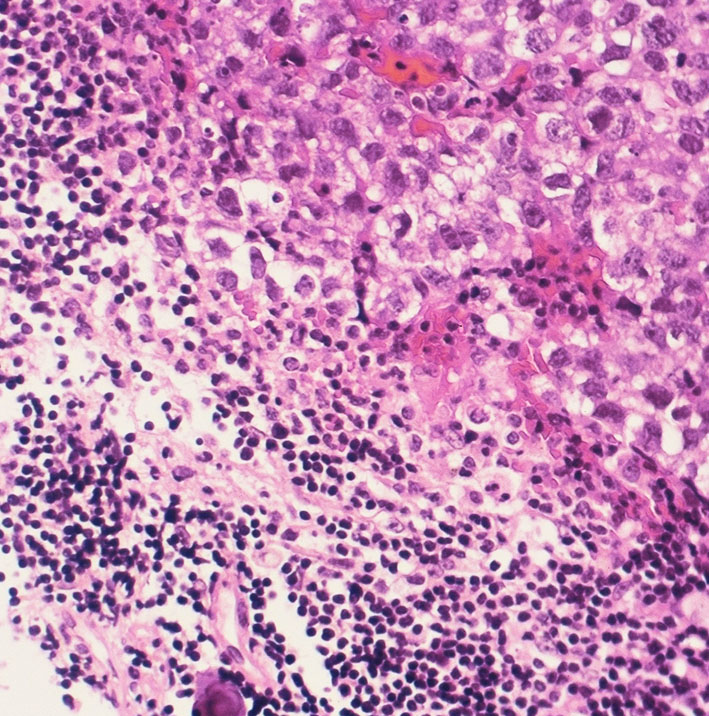

ジャーミノーマ(胚腫)の病理

(ここをクリックするともっとたくさん見えます)

病理診断は困難ではありません。左側の写真のように,多くの場合にHE染色でtwo-cell patternと呼ばれる, 大型の腫瘍細胞と小型のリンパ球浸潤の特徴的な病理像で診断がつきます。大型の腫瘍細胞は楕円形の大きな核に大きな核小体が特徴です。